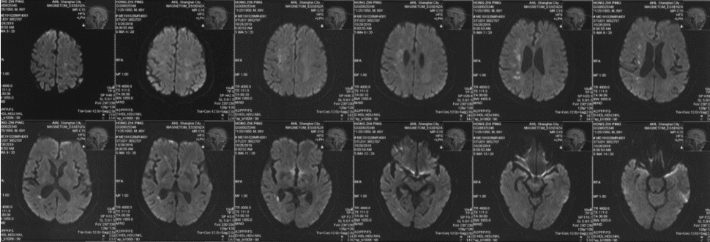

DW-MR(2019-10-30)检查提示分水岭梗死